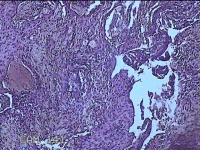

宫颈管组织

性别

女

年龄

33岁

临床诊断

异位妊娠

一般病史

停经52天,阴道流血12天。

标本名称

大体所见

灰白暗红色不规则碎组织4.3x3.3x1.2cm一堆。